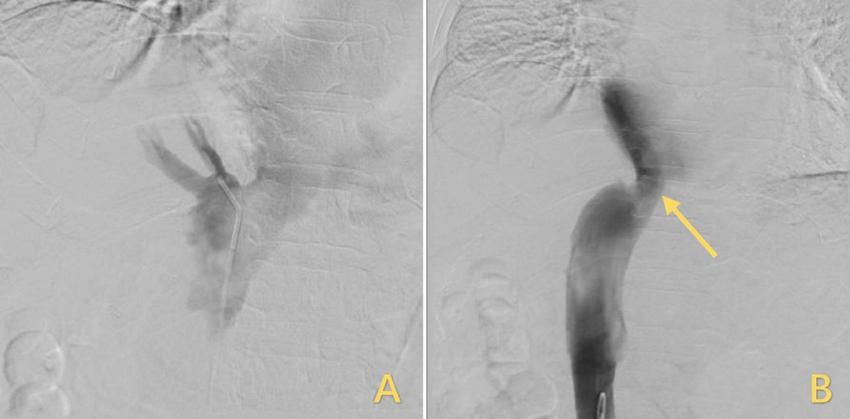

FIGURE 3

Treatment for IVC stenosis with interventional balloon dilatation. (A) The inflated balloon was used to open the narrowed IVC. (B) After the balloon was withdrawn, the IVC returned to its original shape, but the stenosis remained unrelieved, and the arrows highlighted in yellow indicate the stenosis. IVC, inferior vena cava.

However, the patient’s treatment process was not very smooth, and the patient experienced twists and turns. The treatment of BCS began with an interventional approach using a balloon to dilate and shape the stenotic IVC. The patency of the IVC was restored after balloon inflation (Figure 3A), but the original stenosis returned immediately after balloon withdrawal, and there was no change in the internal diameter of the stenosis (Figure 3B). There was no benefit from three rounds of balloon inflation. Postoperative chest radiographs showed a marked elevation of the right diaphragm in contrast to the left diaphragm, which was elevated by approximately three vertebral levels, consistent with a diagnosis of DE (Figure 4A). Subsequently, ultrasound examination of diaphragmatic mobility revealed that during calm breathing, the right diaphragm amplitude was 0.20–0.47 cm and did not change significantly; the left diaphragm amplitude was 2.4 cm; which was consistent with the diagnosis of right DE (Figure 5). Tumors of thoracic and mediastinal origin and those caused by inflammation were ruled out by positron emission tomography/computed tomography (PET/CT). Based on these findings, the CT images were further reviewed. It was suggested that the elevation of the diaphragm led to liver transposition and torsion of the HV at the confluence of the IVC. This approach helped to clarify the distortion of the IVC despite several interventional balloon dilatations due to the external force exerted by liver traction. To prevent further elevation of the diaphragm from worsening the obstruction, DP was recommended by thoracic surgeons. However, the efficacy of this procedure for treating BCS is inconclusive and has not been reported in the literature. Nonetheless, DP minimally invasive, and even if it is ineffective, it does not increase the difficulty of open surgery.